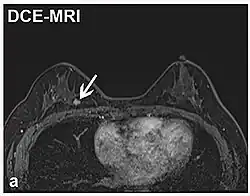

| Marcação de spin arterial | ASL | Marcação magnética do sangue arterial abaixo da área de imagem, que posteriormente entra na região de interesse.[83] Não requer contraste de gadolínio.[84] | |||

| Realce de contraste dinâmico | DCE | Medidas de mudanças ao longo do tempo no encurtamento da relaxação spin-lattice (T1) induzido por um bolo de contraste de gadolínio.[85] | O aumento rápido do contraste de gadolínio, juntamente com outras características, sugere malignidade.[86] | ![]() | |